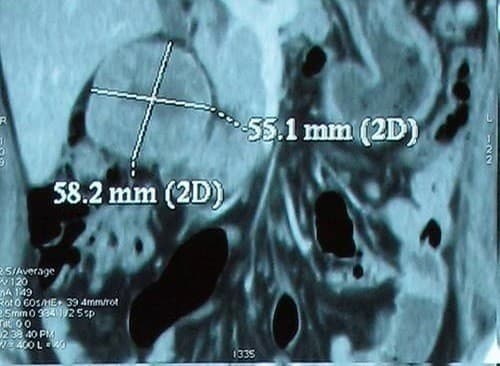

Để quan sát hình ảnh ung thư thận, người bệnh cần thực hiện các phương pháp chẩn đoán như siêu âm hoặc chụp CT…